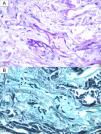

A 16-year-old hospitalized adolescent diagnosed with sickle cell anemia with a 1-day history of 4 purpuric nodules, 5mm in diameter, located on the neck, right upper limb, and abdomen (Fig. 1). The patient had undergone two consecutive hematopoietic progenitor transplants, the last one 9 days prior, and had neutrophil counts of 0 per microliter, so he was on prophylactic therapy with liposomal amphotericin B at 3mg/kg/day. He remained afebrile. The patient had experienced consolidative pneumonia a few days before, with a bronchoalveolar lavage PCR negative for fungi, although the fungal marker galactomannan had increased from 0.17 up to 5.71. Due to suspicion of invasive fungal infection, biopsies were performed for calcofluor staining, histological examination and fungal culture. Blood cultures were also taken. The calcofluor staining revealed fungal structures, so the dose of amphotericin B was increased to 5mg/kg/day, and isavuconazole was added. The hematoxylin–eosin staining showed, in the middle dermis, a group of hyaline and septate hyphae located intravascularly and immediately adjacent to the vessel (Figs. 2 and 3). The fungal culture grew Fusarium verticillioides sensitive to amphotericin B, posaconazole, and voriconazole. Blood cultures all tested negative. Isavuconazole was switched for voriconazole, and filgrastim was administered, resulting in a partial recovery of neutropenia, an excellent clinical response, resolution of the condition, and a reduction in galactomannan levels down to 0.18.

In disseminated Fusarium infections, skin lesions are present in more than 70% of patients.4 These lesions are typically multiple and widespread. They include red or gray macules or papules, some with central necrosis or eschar resembling ecthyma, purpuric papules, pustules, or subcutaneous nodules. This clinical presentation results from thrombosis of dermal vessels by Fusarium hyphae, subsequent extravasation of erythrocytes, and further focal dermal necrosis and epidermal ulceration.1 Patients often present with myalgias and persistent fever unresponsive to empirical antibiotic and antifungal treatment.5

Once the infection has been suspected, the diagnostic process should begin immediately, including biopsy with an immediate fungal stain (such as calcofluor or KOH), histological examination, fungal culture, blood cultures, and radiological tests to assess pulmonary and sinus involvement.1 Blood cultures are only positive in 40% of patients with disseminated fusariosis,6 possibly due to the use of prophylactic antifungals or sample collection conditions. Definitive diagnosis requires histology demonstrating fungal structures inside the vessels, which explains the need for urgent microscopic examination, either with rapid stains or frozen histological sections. Nevertheless, culture is key to identifying the type of fungus (as Aspergillus and Fusarium appear identical under the microscope) and determining its sensitivity.